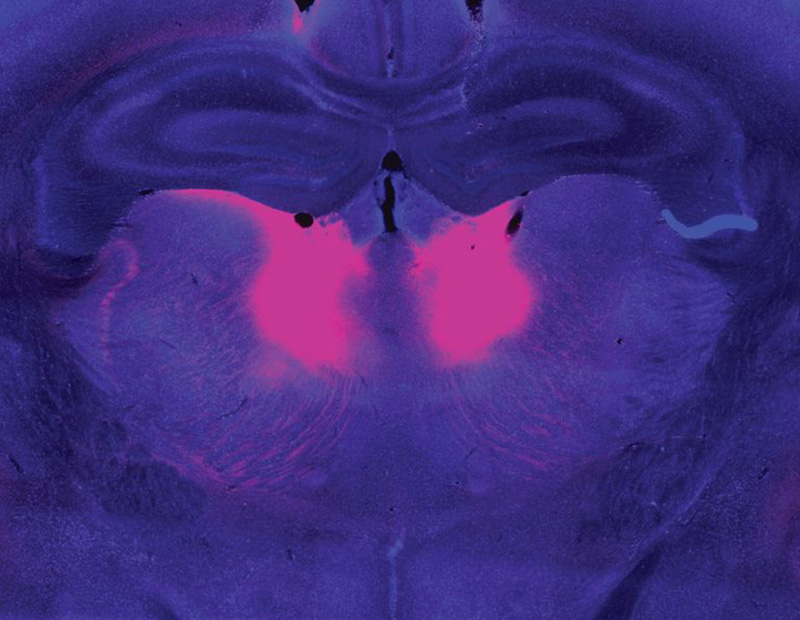

Zhou and Feng linked this behavioral difference to abnormally low activity in a part of the brain called the mediodorsal thalamus. The mediodorsal thalamus acts like a switchboard in the brain, routing and coordinating information between different parts of the cortex to support thinking, decision-making, and flexible behavior. Studies with patients have implicated this region in schizophrenia as well, showing that it has fewer cells and is less active in people with the disorder than those without.

In mice with Grin2a mutations, the researchers were able to restore normal belief updating by activating neurons in the mediodorsal thalamus, offering hope that manipulating the same circuitry might benefit patients. “It will not be easy,” Feng says, “but at least you have something you can work on. Previously, it was just very hard to imagine how to develop a new therapeutic for schizophrenia.”